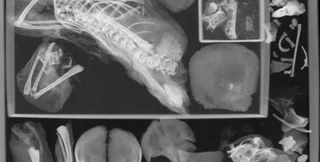

Хоча голова муміфікованої жінки відсутня, її світлина залишилася

Фото: International Journal of Osteoarchaeology

Також у матері відсутня голова, що ускладнює отримання інформації про її загальний стан здоров'я. У розпорядженні вчених, по суті, лише одне фото муміфікованої голови матері, проте ніхто не знає, де вона може перебувати сьогодні. Автори дослідження також планують провести повторну комп'ютерну томографію, вважаючи, що новий раунд може надати додаткові подробиці.